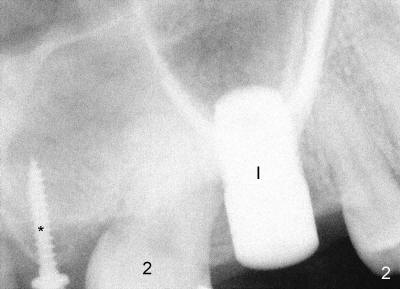

After extraction of the teeth #1,3 and 32, a mini-implant (Fig.2 *) is placed as anchorage to distalize #2. Space is created for #3 implant in 3 months. A 7x14 Tatum screw implant is placed as deep as possible with sinus lift (I).